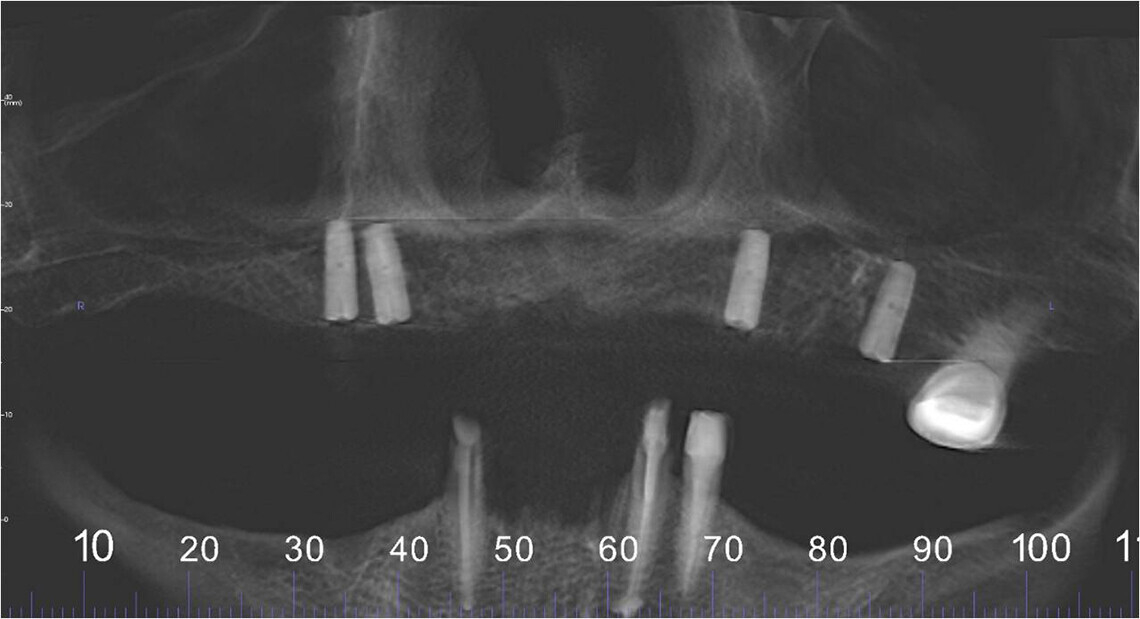

Съемная часть протеза надежно фиксируется на опорных зубах и имплантатах, покрытых первичными коронками. Опорные зубы или имплантаты при использовании бюгельного протеза на телескопических коронках не перегружаются.

Прочность фиксации конструкции зависит от количества опорных зубов или имплантатов. Для более надежной фиксации и продолжительного срока службы бюгельной конструкции требуется установка на челюсти не менее шести телескопов. Однако, чтобы зафиксировать телескопические протезы, достаточно двух опорных зубов или имплантатов.